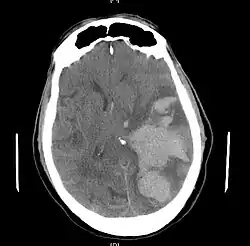

Cerebral herniation

MRI showing injury due to brain herniation

MRI showing damage due to herniation. This patient was left with residual disabilities including those involving movement and speech.[16]

Treatment involves removal of the etiologic mass and decompressive craniectomy. Brain herniation can cause severe disability or death. In fact, when herniation is visible on a CT scan, the prognosis for a meaningful recovery of neurological function is poor.[2] The patient may become paralyzed on the same side as the lesion causing the pressure, or damage to parts of the brain caused by herniation may cause paralysis on the side opposite the lesion.[11] Damage to the midbrain, which contains the reticular activating network which regulates consciousness, will result in coma.[11] Damage to the cardio-respiratory centers in the medulla oblongata will cause respiratory arrest and (secondarily) cardiac arrest.[11] Investigation is underway regarding the use of neuroprotective agents during the prolonged post-traumatic period of brain hypersensitivity associated with the syndrome.[17]